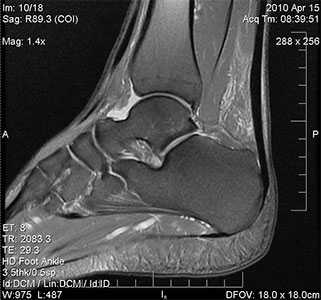

МРТ голеностопного сустава

Порой припухлость окружающих тканей настолько сильная, что оценить сустав становится сложно. В этом случае в качестве вспомогательных мер используются УЗИ, МРТ, рентгенография.

МРТ для диагностики недуга не является обязательным исследованием. Его выполнение рекомендуется, если необходимо провести дифференциальную диагностику с другими патологиями либо в начальных стадиях патологии.